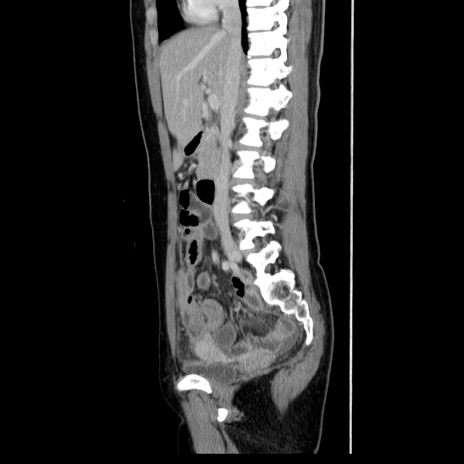

症例39(矢状断像)

【症例】40歳代女性

【主訴】上下腹部痛

【現病歴】2日目から下腹部痛あり。夜間は痛みで眠れなかった。昨日より上腹部痛と下痢が出現。臥位で痛みは軽快したため、休んでいた。本日になって臥位でも立位でも痛みが強くなってきたため救急要請。

【既往歴】子宮内膜症

【身体所見】部:平坦・軟、左上下腹部に圧痛あり、反跳痛あり。

【データ】WBC 21800、CRP 26.78

CT